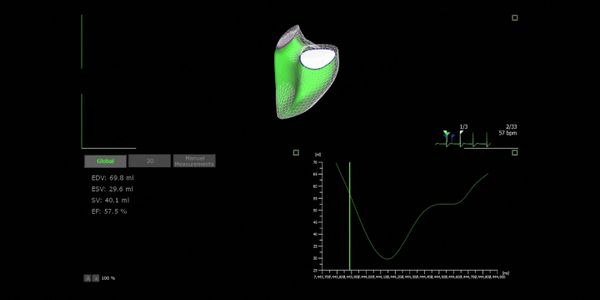

Acum poti reduce drastic numarul de pasi pentru calcularea FE (Fractie de Ejectie). Tehnologia IA recunoaste automat cadrele diastolice si sistolice, si masoara FE pe baza metodei Simpson. Nu mai este nevoie sa cauti manual printre cadre si sa le alegi pe cele mai potrivite, pentru ca sistemul face asta pentru tine - repede si precis.

Utilizeaza analiza 4D LV pentru evaluarea functiei VS cu ajutorul functiei 3D speckle tracking (contrast 3D). Aceasta abordare inovativa de cercetare expune analiza strain globala si regionala via modelul 3D a VS, care vizualizeaza miscarile peretelui cardiac in mod comprehensiv; in acelasi timp, codificarea prin culoare subliniaza ariile sanatoase sau problematice in diferite segmente. Iti aduce in final mai multa informatie despre miscarea anormala a peretelui cardiac si functiei cardiace.